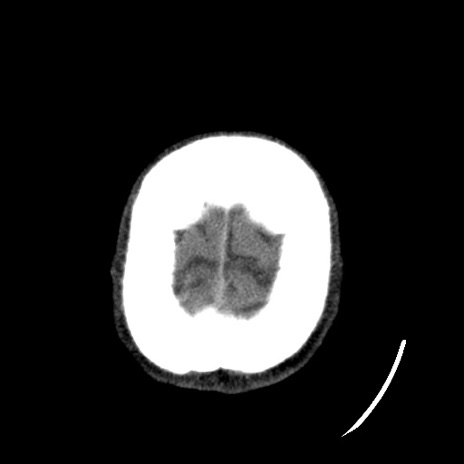

【顔面】症例16 横断像

【症例】20歳代 男性

【主訴】頭部打撲

【現病歴】本日バイクに乗っていたところ、前に止まっていたトラックと接触し、転倒。救急搬送となる。

【身体所見】意識清明、瞳孔径3mm/3mm、対光反射+/+、右下顎部のしびれ、知覚低下あり。